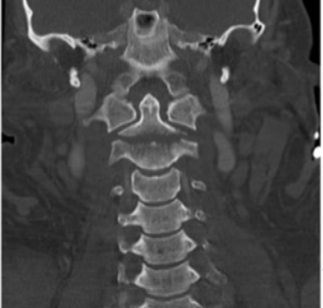

Fratura do processo odontoide

Tipo III de Anderson e D’alonzo.

Envolve o corpo de C2.

Estável, melhor prognóstico;